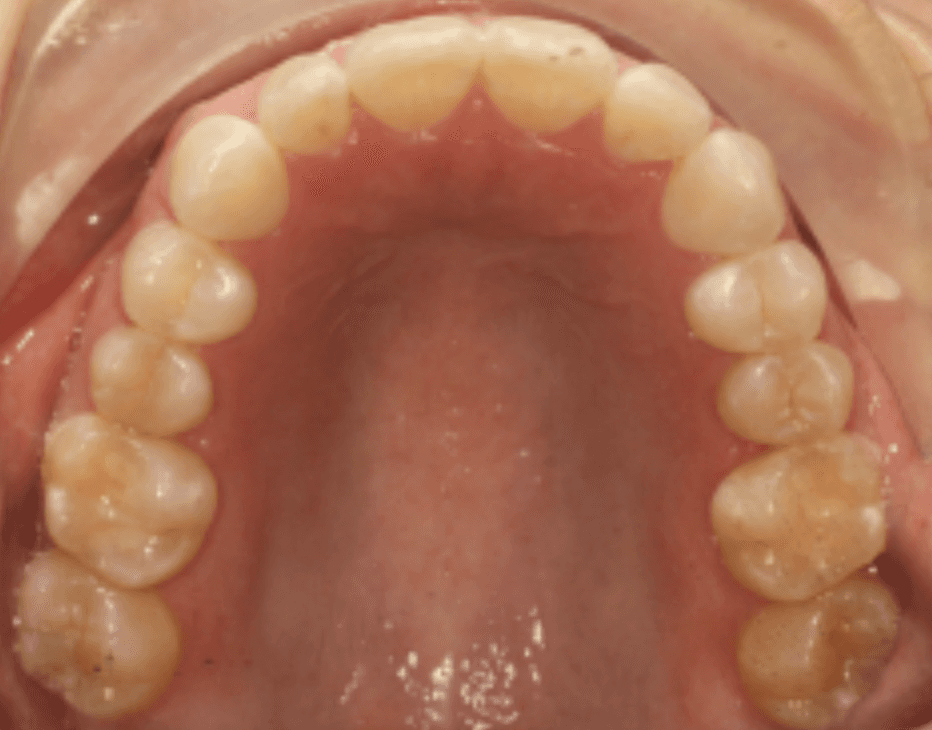

Final results

INTRAORAL